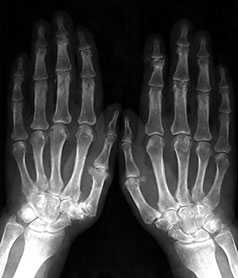

Костно-суставная система кистей и дистальных отделов стоп является основным объектом исследования для постановки диагноза и определения стадии ревматоидного артрита (РА) и проведения дифференциального диагноза с другими заболеваниями ревматической и неревматической природы.

Синовиальная оболочка периферических суставов является органом-мишенью, где при РА разворачивается хроническое аутоиммунное воспаление, приводящее в дальнейшем к характерному для РА множественному и симметричному поражению суставов. Симметричность изменений в суставах кистей и стоп является отличительной особенностью РА. Типичные признаки РА – симметричное поражение пястно-фаланговых и плюсне-фаланговых суставов, суставов запястий, проксимальных межфаланговых суставов кистей. Первые рентгенологические симптомы артрита, в т. ч. и появление первых эрозий, могут обнаруживаться во 2-х и 3-х пястно-фаланговых суставах, 3-х проксимальных межфаланговых суставах кистей, суставах запястий, лучезапястных суставах, шиловидных отростках локтевых костей, 5-х плюсне-фаланговых суставах. При более выраженных стадиях РА изменения могут обнаруживаться в дистальных межфаланговых суставах кистей и стоп. РА никогда не начинается с поражения дистальных межфаланговых суставов кистей и стоп, проксимальных межфаланговых суставов стоп.

Наиболее часто в повседневной практике применяется рентгенологическая классификация, основанная на делении РА на модифицированные стадии по Штейнброкеру с использованием обзорных рентгенограмм кистей и дистальных отделов стоп в прямой проекции.

Выделяются 4 рентгенологические стадии РА, отражающие прогрессирование симптомов артрита в суставах кистей и дистальных отделов стоп.

К 1-й стадии (ранним рентгенологическим изменениям) РА относятся периартикулярное утолщение и уплотнение мягких тканей, околосуставной остеопороз (повышение рентгенпрозрачности костной ткани), единичные кистовидные просветления костной ткани и сужение отдельных суставных щелей в типичных для начального РА суставах. Рентгенологические симптомы 1-й стадии неспецифичны для РА и могут быть обнаружены при других ревматических заболеваниях, что требует обязательного учета клинико-лабораторных показателей заболевания.

Стадия 2 характеризуется нарастанием околосуставного остеопороза, появлением множественных кистовидных просветлений костной ткани в эпифизах коротких трубчатых костей и костях запястий в сочетании с множественными сужениями суставных щелей, эрозивными изменениями в суставах и небольшими краевыми деформациями костей. Эта стадия подразделяется на неэрозивную и эрозивную формы в зависимости от отсутствия или наличия деструктивных изменений в суставах. Как правило, первые эрозии появляются во 2–3-х пястно-фаланговых, 5-х плюсне-фаланговых суставах, костях запястий, в области шиловидного отростка локтевой кости. Отличительная особенность 2-й стадии РА – отсутствие умеренных или выраженных деформационных изменений, подвывихов, вывихов и костных анкилозов суставов.

Стадия 3 характеризуется нарастанием рентгенологических симптомов, выявляемых при 2-й стадии. Деструктивные изменения выраженные, определяются во многих суставах кистей и дистальных отделов стоп. Преобладают в типичных для РА суставах. Отличительная особенность 3-й стадии – умеренные и выраженные деформации эпифизов костей, подвывихи и вывихи в отдельных или многих суставах.

4-я стадия характеризуется симптомами 3-й стадии и появлением костных анкилозов суставов. Для РА типичны анкилозы в суставах запястий (межзапястных, 2–5-х запястно-пястных суставах). Крайне редко выявляются анкилозы в проксимальных межфаланговых суставах кистей и лучезапястных суставах. Выраженные деструктивные изменения в костях запястий могут приводить к коллапсу запястий, который характеризуется снижением высоты запястий, выраженными деформациями, уменьшением размеров или остеолизом костей запястий. Остеолитические изменения могут выявляться в пястно-фаланговых и, реже, плюсне-фаланговых суставах. Рентгенологические стадии РА представлены на рисунках 1–11.